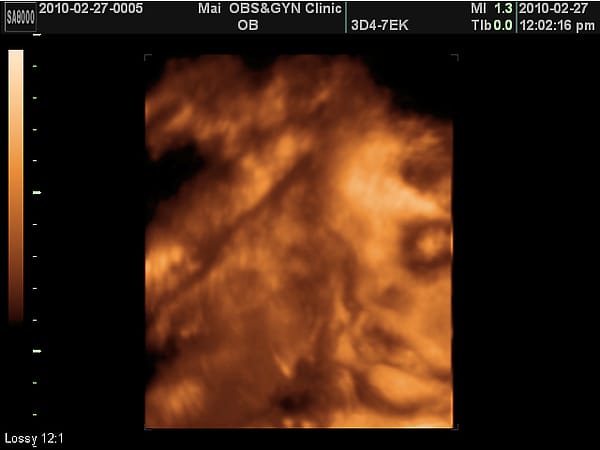

目前小老虎已就定位,這個位置羊水不夠多看不太清楚小老虎,但是呢,看起來眼窩黑黑滴,嘴唇厚厚低。